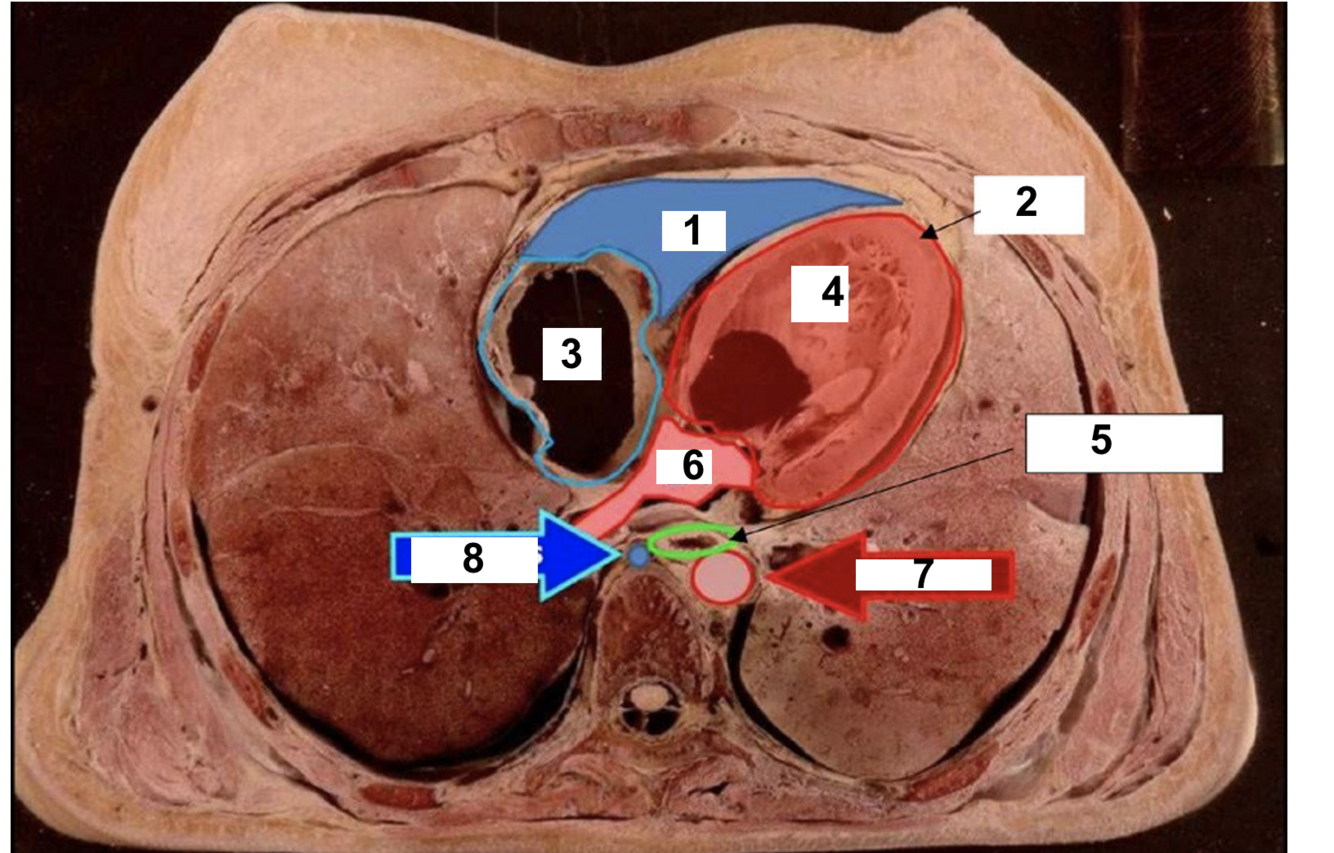

14

label 1

A

15

2

16

3

17

4

18

5

19

6

20

7

21

8